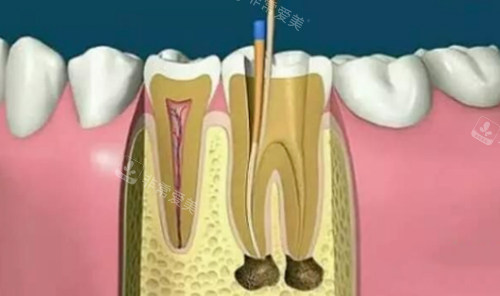

根管治疗动画演示

磨牙作为口腔咀嚼核心,根管数量通常达3-4个,部分复杂病例甚至有5-6个变异根管,加上位置靠后、操作空间狭小,治疗耗时是前牙的2-3倍,价格自然处于高位。显微根管治疗因借助专科设备提升成功概率,费用比常规治疗高出30%-50%。

根管数量是定价的核心依据,前牙多为单根管,前磨牙1-2个,磨牙3-4个,每增加一个根管,治疗步骤、材料消耗都会相应增加,费用随之上涨。